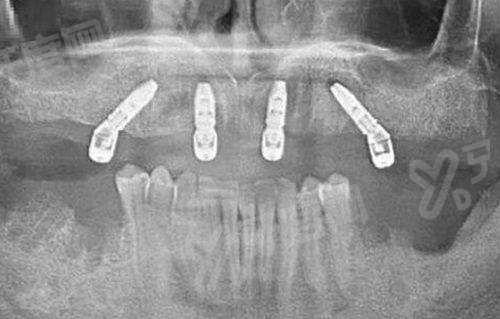

李东益医生擅长的项目非常广泛。在牙齿矫正方面,他能够根据患者的牙齿情况和面部特征,制定个性化的矫正方案,无论是传统的金属矫正,还是隐形矫正,他都能熟练操作,帮助患者拥有整齐美观的牙齿。在种植牙领域,李东益医生有着高超的技术,他可以精细地植入种植体,提高种植牙的成功几率和稳定性,让患者重新拥有健康的咀嚼功能。此外,他在牙齿美容修复、牙周病治疗等方面也有着丰富的经验和出色的技术。

李东益医生紧跟口腔医学的发展趋势,不断引进和掌握精良的技术。在牙齿矫正中,他采用数字化正畸技术,能够更严谨地分析牙齿的移动轨迹,缩短矫正时间。在种植牙手术中,他运用精良的导航系统,提高种植的精细度,减少手术创伤。同时,他注重与患者的沟通,会耐心地向患者解释治疗方案和过程,让患者在治疗过程中更加安心。